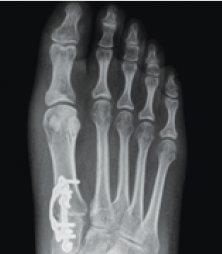

What Does A Correction Look Like On X-Ray?

xray Normal Foot

xray Traditional 2D Surgery

"Cut & Shift" approach leaves an unstable joint

xray Lapiplasty® 3D Bunion Correction™

Alignment is restored & unstable joint is permanently secured